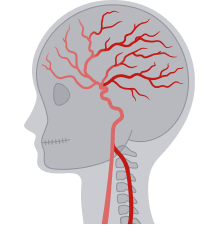

腦血管系統供血不足影響神經功能

前循環指的是頸動脈供應的血流,主要負責大腦前部的供血,包括額葉功能。

後循環由椎動脈經脊椎進入,供應大腦後部和平衡中樞。